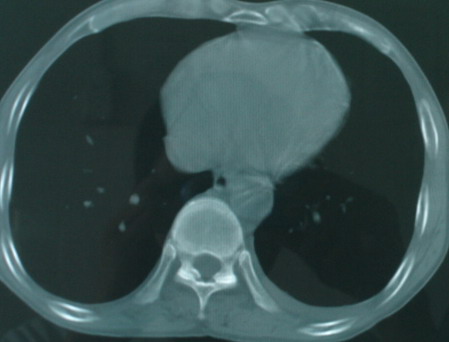

以下是引用医影拾贝在2008-6-3 18:48:00的发言:[br]双上肺弥漫性小结节影,纵隔窗内钙化淋巴结影,考虑血播性tb可能性较大,不除外肺ca可能

以下是引用卜一在2008-6-3 19:33:00的发言:[br]双肺结节,以双上肺分布为多,期间搀杂片状致密影及索条致密影。考虑:继发性肺结核伴血型播散可能性大。不除外肺泡ca的可能!另:椎体退变!

以下是引用panyishengct在2008-6-3 21:09:00的发言:[br]双上肺弥漫性小结节影,纵隔窗内钙化淋巴结影,考虑矽肺或/和tb可能性较大,不除外肺ca可能。腰椎考虑退变。 [br][br]